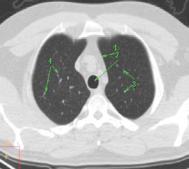

Рис. 24. КТ на уровне бифуркации

трахеи в легочном электронном окне: 1 – просвет правого главного бронха;

2 – правый верхнедолевой бронх; 3 – передний сегментарный

бронх верхней доли правого легкого; 4 – субсегментарный бронх;

5– просвет бронха V-го порядка;

6– левый главный бронх;

7– поперечные сечения сегментарных бронхов;

8– сечения сосудов в различных плоскостях